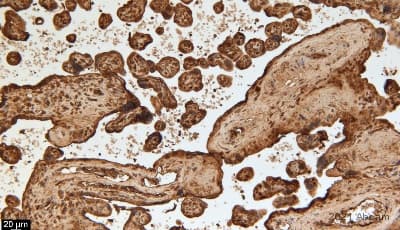

Anti-Fibrinogen antibody ab34269 is a rabbit polyclonal antibody that is used in Fibrinogen IHC and immunofluorescence. Suitable for human and mouse samples.

Applications FuncS, ICC/IF, IHC-P, sELISA

Species Reactivity Human, Mouse, Rabbit